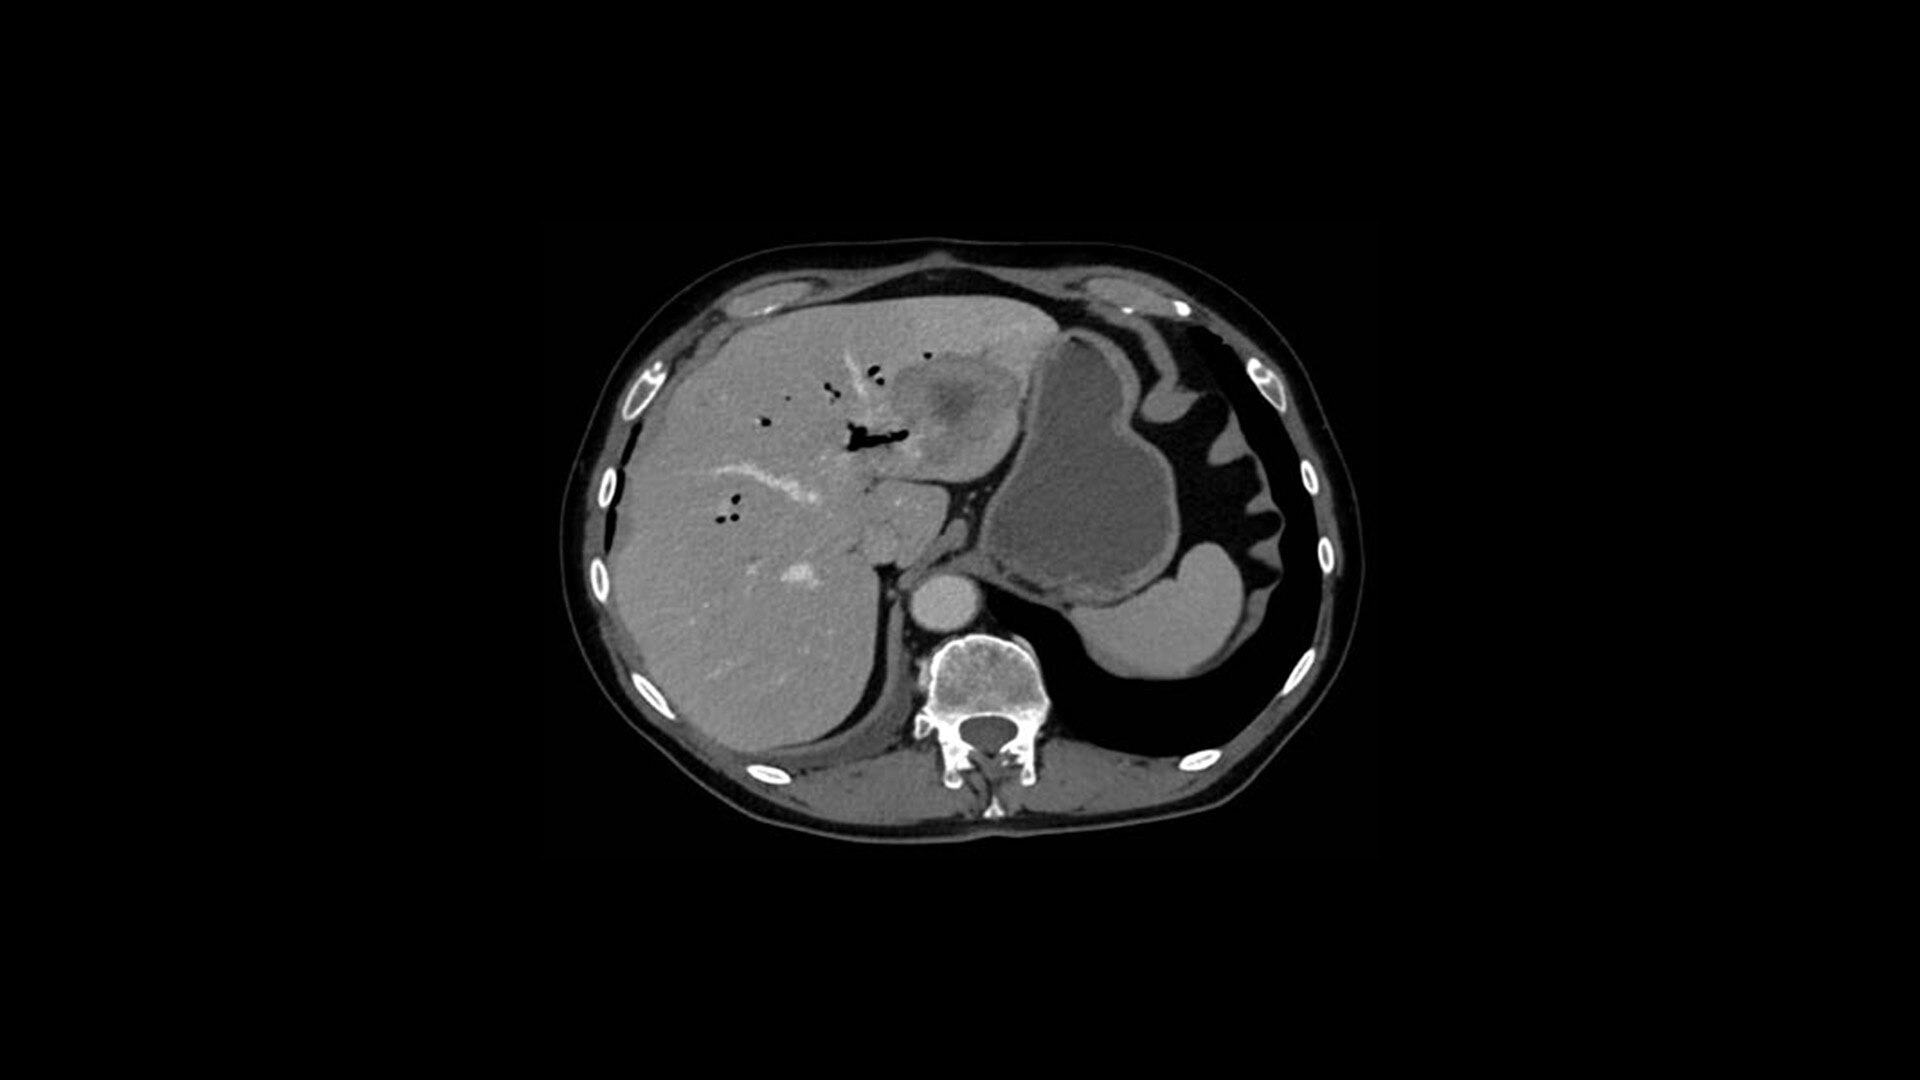

TrueFidelity DL

Deep learning for a deeper understanding

TrueFidelity™ DL is our state-of-the-art image reconstruction technology that uses a DNN to generate high-definition, low-noise CT images. It produces images with exceptional sharpness, low-contrast image quality performance and your preferred noise texture, at the same dose.¹